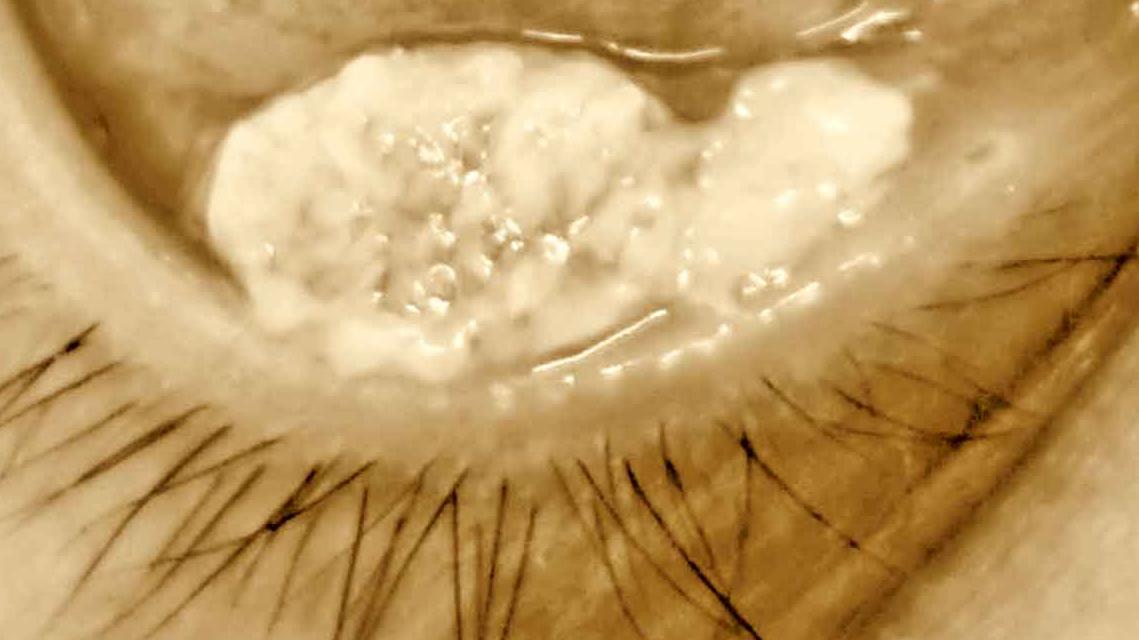

鱗狀細胞癌

痱滋四星期未癒?六大頭頸癌症狀要留意!

• 眼瞼腫瘤

生粒癦都有致命風險?眼周皮膚異常可能是癌症!